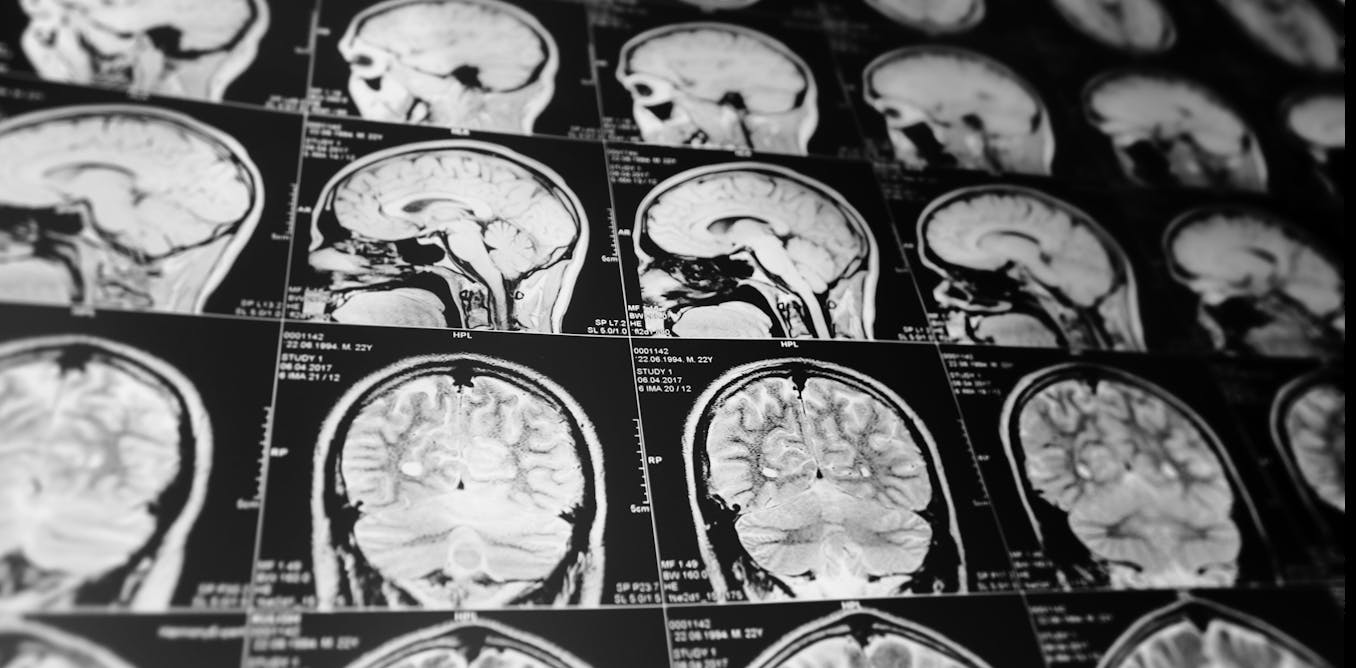

We screened the DNA and closely examined magnetic resonance imaging (MRI) scans from more than 70,000 people across 19 countries. We wanted to find out if there are specific genetic variants influencing differences in brain size between individuals.